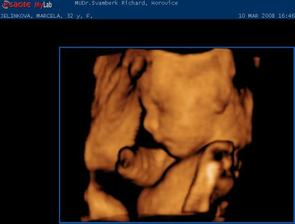

Jako v pohádce. 1.9.2007 jsme měli svatbu. 18.9.2007 jsme odjeli do Egypta na svatební cestu. Ze které jsme přijeli ve třech. Opravdu se nám to povedlo. 7.10.2007 jsem nedostala MS 10.10.2007 HURÁ !!!! Těhoteský test pozitivní. 12.11.2007 první KO, jsem 9+1 tt. Pan doktor mi dělal UTZ, dal mi první fotku mimíška. Těhotenství potvrzeno na 100 %,dostala jsem Těhotenskou průkazku. 29.11.2007 11+6 tt Byla jsem na odběru krve. Mám nízký tlak. 10.12.2007 13+3 tt KO viděla jsme opět mimíško na UTZ, má se čile k světu. Krev je vpořádku. 13.12.2007 potvrzení od obvodní lékařky a měření EKG. 3.1.2008 16+4 tt KO odběr krve na Triple test. UTZ mimíšku pěkně bije srdíško. Mám stále nízký tlak. Berou mě křeče do lýtek a pálí žáha. Pan doktor mi napsal MagneB6. 19.1.2008 18+6 tt už se pomalu do ničeho nevejdu. První nákup těhu kalhot a těhu blůza. 22.1.2008 19+2 tt dnes ráno jsme cítila jak mě mimíško několikrát koplo. A dopoledne v práci jsem cítila takové šimrání v bříšku. 28.1.2008 dneska jsem koupila mimíškovi první bodíčka. 31.1.2008 20+4 tt KO Trile test nagativní. Pan doktor mi dělal UTZ a pravděpodobně to bude KLUK. Poznala jsme to i já. Mimíško už váží 400g. Manžel měl radost. 4.2.2008 21+1 tt první těhotenské plavání. Bylo to moc pěkné a myslím, že i mimíšku v bříšku se to líbilo. 9.2.2008 – 16.2.2008 mám dovču. Jeli jsme na hory, ale já jsme raději nelyžovala, abych neublížila mimíšku. Vynahradím si to až příští rok. Hodně jsem odpočívala a chodila na procházky. 18.2.2008 kontrola u zubaře. Vše v pořádku. 19.2.2008 v práci mi bneska hodně tvrdlo a bolelo břicho. Tak uvidím jak mi bude zítra. 20.2.2008 23+3 tt opět mě tvrdlo a bolelo břicho až do zad. A docela intenzivně. Popráci jsem šla rovnou k doktoru. Vyšetřil mě a říkal, že to není moc dobré. Raději mi napsal neschopenku. 21.2.2008 bolí mě v kříži, především při chůzi. Jen doufám, že to nebude až do konce těhulkování. 27.2.2008 24+3 tt dneska jsem šla k obvodní doktorce s tou bolavou kyčlí. Stále mě dost bolí. Poslala mě na těhotenské cvičení, kde mi ukážou nějaké uvolňovací cviky a mám odpočívat. Snad to přejde. 5.3.2008 25+3 tt těhotenaké cvičení v nemocnici. Sestřička mi ukázala nějaké cviky na uvolnění kyčle a masáž. 10.3.2008 26+1 tt dneska jsme byli s manželem na 4 D UTZ. Bylo to moc hezké, mimíško se nám hezky ukázalo. Dokonce jsme viděli, že je to opravdu kluk. Pan doktor nám udělal nějaké fotky a nahrál mimíško na DVD. Je to opravdu moc krásný a jedinečný zážitek. 11.3.2008 26+2 tt dnes jsem byla v nemocnici na testu na cukrovku. 13.3.2008 začala jsme chodit do Solné jeskyně. Moc pěkně se tam relaxuje. Rozhodně to všem doporučuji. 19.3.2008 Dnes velký nákub oblečků na mimíško. 20.3.2008 27+4 tt KO test na cukr mám v normě. Tlak stále nízký a žáha mě pořád pálí. Bolest kyčle už ustoupila. Parvděpodobně mimíško změnilo polohu a netlačí už na nic. 29.3.2008 Byli jsme se podívat na kočárek. Nakonec se nám nejvíce líbí kočárek JANE SLALOM PRO, barva hnědooranžová. 10.4.2008 začala jsme chodit na těhu cvičení na Gymbalonech. 16.4.2008 první hodina předporodní přípravy. 17.4.2008 31+4 tt KO UTZ mimíško podle měření už váží 2100g, doufám, že to nebude žádný obřík. Jinak se má k světu a vše je v pořádku. Byla mi odebrána krev. 25.4.2008 32+5 tt pěkně mě bolí v krku. Návštěva obvodní lékařky. Udělala mi výtěr a uvidí podle výsledků. 28.4.2008 výtěr je vpořádku, ještě mě pro jistotu poslala na krční. Prý v těhotenství bývají zduřelé krční mandle. Tak by to mělo přejít samo. Mám brát pouze těhu vitamíny. Dneska jsme si přivezli kočárek. Nechali jsme ho u rodičů, pro jistotu, pověra je pověra, ale kdo ví. 4.5.2008 34 tt nástup na mateřskou dovolenou. Začínám s masáží hráze. 5.5.2008 34+1 tt KO UTZ mimíško už tam nemá moc místa, váží už 2500g, Mám nízké hodnoty železa v krvi. Tak jsem dostala vitamín železo. Magnesium už nemám brát. Dneska jsme byli s manželem v nemocnici, kde budu rodit, na předporodní besedě. Řekli nám, co nás čeká při porodu, a ukázali porodní pokoj. 8.5.2008 doma generální úklid a příprava na mimíško. Oblečky na mimíško mi pere a žehlí mamka, je moc hodná a hodně mi s tím pomáhá. Jsem moc ráda a tato práce mi odpadla a já si domů odvezu už vše hotové. 9.5.2008 34+5 tt celou noc jsem nespala, mám rýmu a strašný kašel. Docela se bojím i o mimíško. Tak jsem raději šla k obvodní doktorce. Ta mě poslechla, mám zánět průdušek. Dala mi antibiotika ZINNAT 250mg. Moc nejsem nadšená. Ujišťovala mě, že se můžou v těhotenství, a i v lékárně mi to říkali. Doma jsem si to našla i na Internetu. Tak snad bude vše vpořádku. 12.5.2008 35+1 tt Dneska jsem byla na natočení na EKG, to prý potřebuji k porodu. 13.5.2008 Opět mě začal bolet kyčel, jak mě již jednou bolel. Asi se mimíško nějak jinak uvelebuje a tlačí mi na nějaký nerv. 15.5.2008 35+4 tt KO doktor říkal, že mě ta kyčel pravděpodobně přestane bolet až po po porodu. Tak nejsem moc šťastná, protože je to dost omezující, především při chůzi. Mimíško je vpořádku. Dneska mi poprvé natáčel monitor, tak jsem slyšela tlukot mimíškova srdíčka. 26.5.2008 37+1 tt Dneska mám narozeniny!!! KO pan doktor mi dělal vyšetření a kultivaci z pochvy. Od příštího týdne už budu chodit na KO do nemocnice, kde také budu rodit. Tak už jsme se rozloučili a mám k němu přijít na KO až po šestinedělí. Snažím se, co nejvíce odpočívat. 2.6.2008 38+1 tt KO už v nemocnici. Výsledky kultivace nejsou moc dobré, tak jsem dostala globule na zavádění. S paní doktorkou jsme se domlouvali na průběhu porodu, protože jsem v minulosti měla zlomenou sedací kost. Domluvili jsme se, že porod necháme přírodní cestou a pokuď bude něco špatně, tak přistoupí k císařskému řezu. Doufám, že bude vše bez komplikací. Opět mi natáčeli monitor. 9.6.2008 39+1 tt KO natáčení monitoru. Je moc hezké slyšet jak mimíšku bije srdíčko. Dneska mi dělala vyšetření, vše je vpořáku. Zítra jdu na UTZ. 10.6.2008 39+2 tt dneska jsem byla na UTZ, kde měřili mimíško. Podle měření váží asi 3509g. Nakonec jsme se s paní doktorkou domluvili, že pokud neporodím do 22.6., tak si v pondělí 23.6. v 8 hodin půjdu lehnout do nemocnice, abych moc dlouho nepřenášela a mimíško nebylo moc velké, vzhledem k té zlomené sedací kosti. No nějak mi to těhulkování moc rychle uteklo a už se ten obávaný porod opravdu blíží, což si nějak moc nechci připouštět. Ale můžu říci, že jsem si to moc užila a ještě užívám. Je to asi opravdu ta nejkrásnější doba v mém životě. Vědět, že v sobě máte mimíško, a těšit se na něj. 16.6.2008 40+1 tt tak dneska už jsme byla na natočení monitoru a na poslední KO. Doktorka mi dělala vyšetření a říkala jak miminko je hezky sestouplé. Prý je dobře připraveno k porodu a vše vypadá, že bych mohla porodit dříve než v pondělí. Aby mi nemuseli porod vyvolávat. Já bych raději chtěla porodit normálně bez vyvolání. Doufám, že se to povede. Jinak v pondělí 23.6.2008 nastupuji do nemocnice. No tak musíme doma zkusit osvědčené babské rady, snad se nám to povede. Mimíško se nějak v bříšku zabydlelo a vůbec se mu nechce ven. Držte nám palečky. Děkujeme. 17.6.2008 40+2 tt od 23.00 hod tvrdnutí bříška, že by to již bylo ono???? Ve 23.43 hod začínají kontrakce po 10 minutách. 18.6.2008 40+3 tt ve 2.30 hod odjezd do porodnice. Kontrakce po 4,5 minutách. V 8.29 hodin DAVÍDEK na světě. Váží 3880g a měří 52 cm. Tatínek byl u porodu a byl moc velkou oporou mamince. Moc si toho vážím. Je to velká odměna a stálo to za to. Těď už jsem ne dva, ale tři. Jedna velká rodina. Jsme moc šťastni.